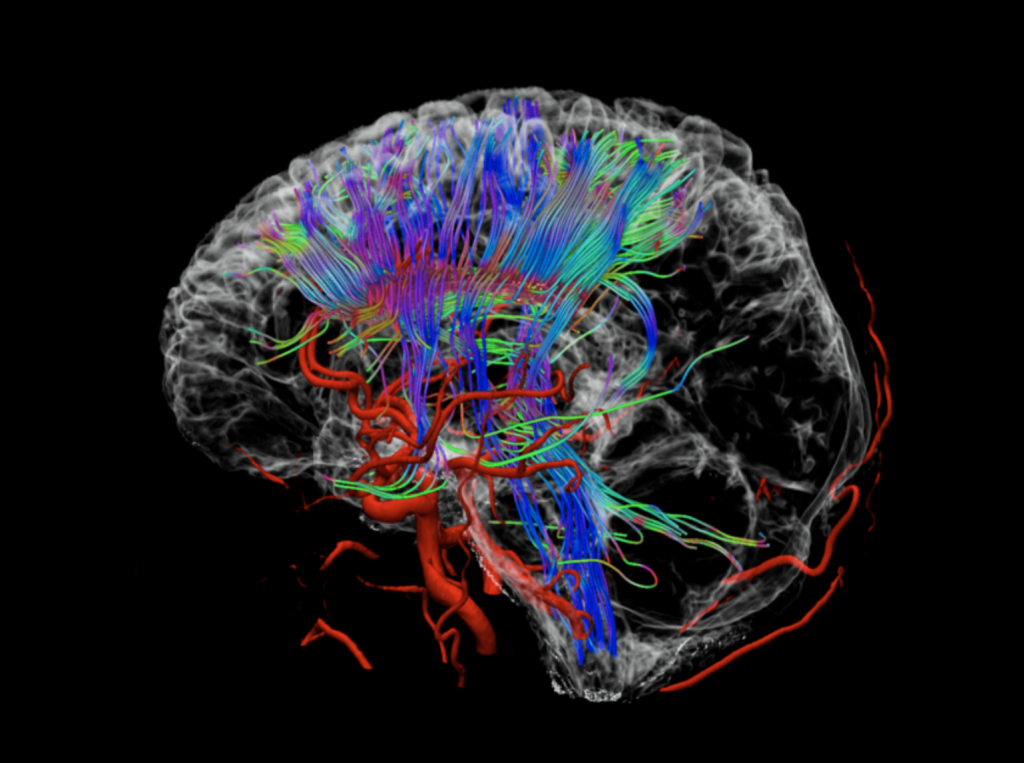

脑卒中磁共振筛查

专为老年人群提供精准的脑卒中早期预警解决方案,应用3D TOF MRA等全新的无损伤性血管成像技术,更清晰显示远端及细小血管,无需注入对比剂,更适用于早期脑血管病变预防与诊断。应用联影光梭3.0T磁共振特有的uCS-DWI序列,是急性脑梗死最敏感的序列

超早期卒中预警:DWI序列能在发病数分钟内显示急性梗死灶,实现超早期诊断;SWI序列可敏锐发现常规扫描难以显示的微出血灶,为血管风险评估提供关键依据。

脑血管系统全景评估:MRA无需造影剂即可清晰显示颅内主要动脉的形态、狭窄或闭塞情况,结合SWI对微小血管病的评估,实现从大血管到微血管的综合筛查。

脑结构与病变精准分析:一站式全面评估脑实质、脑室系统及病灶。对脑梗死分期、脑肿瘤鉴别、脑出血演变、动静脉畸形、颅内血肿等具有重要诊断价值,为治疗方案选择与预后判断提供全面影像学依据。